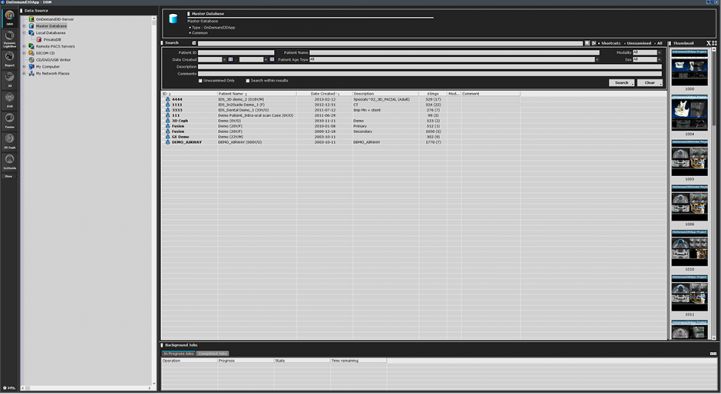

DBM – Manager baze de date

Permite gestionarea eficienta a datelor pacientului, cautarea in baza de date, dupa nume, data, modalitate sau cuvant cheie, vizualizarea miniaturilor, conectarea de la orice calculator sau server de la distanta.

Modulul DBM ofera trei tipuri diferite de accesare a bazei de date. Datele pot fi solicitate si salvate, in orice moment, prin toate cele trei tipuri accesari. Mai mult, datele pot fi copiate de la un sistem la altul.

Functionalitati: DICOM management, cautare date, salvare CD/DVD/USB, import/export pe server, integrare PACS server.